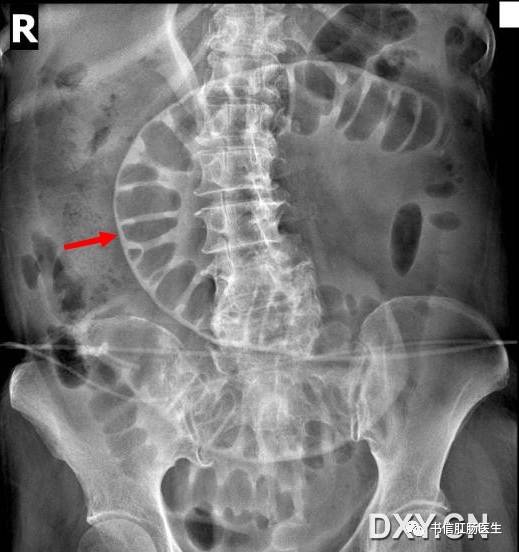

6.双壁征

★ 气腹衬托下肠道外壁也可以清晰显示(红箭头)

■ 影像表现:在仰卧位腹部 X 线平片上,胃肠道腔内气体显示内壁的同时,气腹可将胃肠道外壁显示出来。

■ 征象解析:正常情况下气体仅显示肠壁内腔表面的轮廓而不显示浆膜表面,胃肠道外壁的密度类似邻近腹腔的内容物。而当腹腔内有适量的自由气体存在时,这些自由气体更可能集中在肠撵间,因此可以见到肠管的外壁,这就是双壁征的典型表现。当肠腔充满液体,内壁不可见,只有外侧壁是可见时,表现为不典型的双壁征。

■ 讨论:气腹的出现常提示病变严重,是急诊观察中应引起注意的征象,故认识其在常规的腹部 X 线平片表现非常重要。气腹常见的病因学有 4 种:医源性、自发性、外伤性和其他各种原因。气腹临床表现不特异,有的根本没有症状,也有的有明显的腹膜刺激征,因此详细询问病史很重要。

研究表明发现少量腹腔游离气体敏感的方法是腹部立位平片,能迅速发现膈下游离气体。对不能站立的患者,一种替代方法是左侧卧位,优质的侧卧位片与立位片一样,能发现 <1 ml 的腹腔游离气体。CT 能发现 1 ml 的游离气体,并帮助证实平片可疑的气腹。气腹有许多可能的平片表现,最普通的征象是右隔下游离气体,因为肝脏高密度轮廓的勾画使其表现比较明显。

双壁征有时能被邻近的肠襻干扰,因而在肠襻的内部也可出现相邻肠襻壁的轮廓,导致误诊为游离气体。腹部 CT 中少数剩余的增强剂覆盖在肠腔内表面也可增加肠壁密度形成假双壁征。对于不明确的病例,可通过左侧卧位照片或腹部立位片来证实。